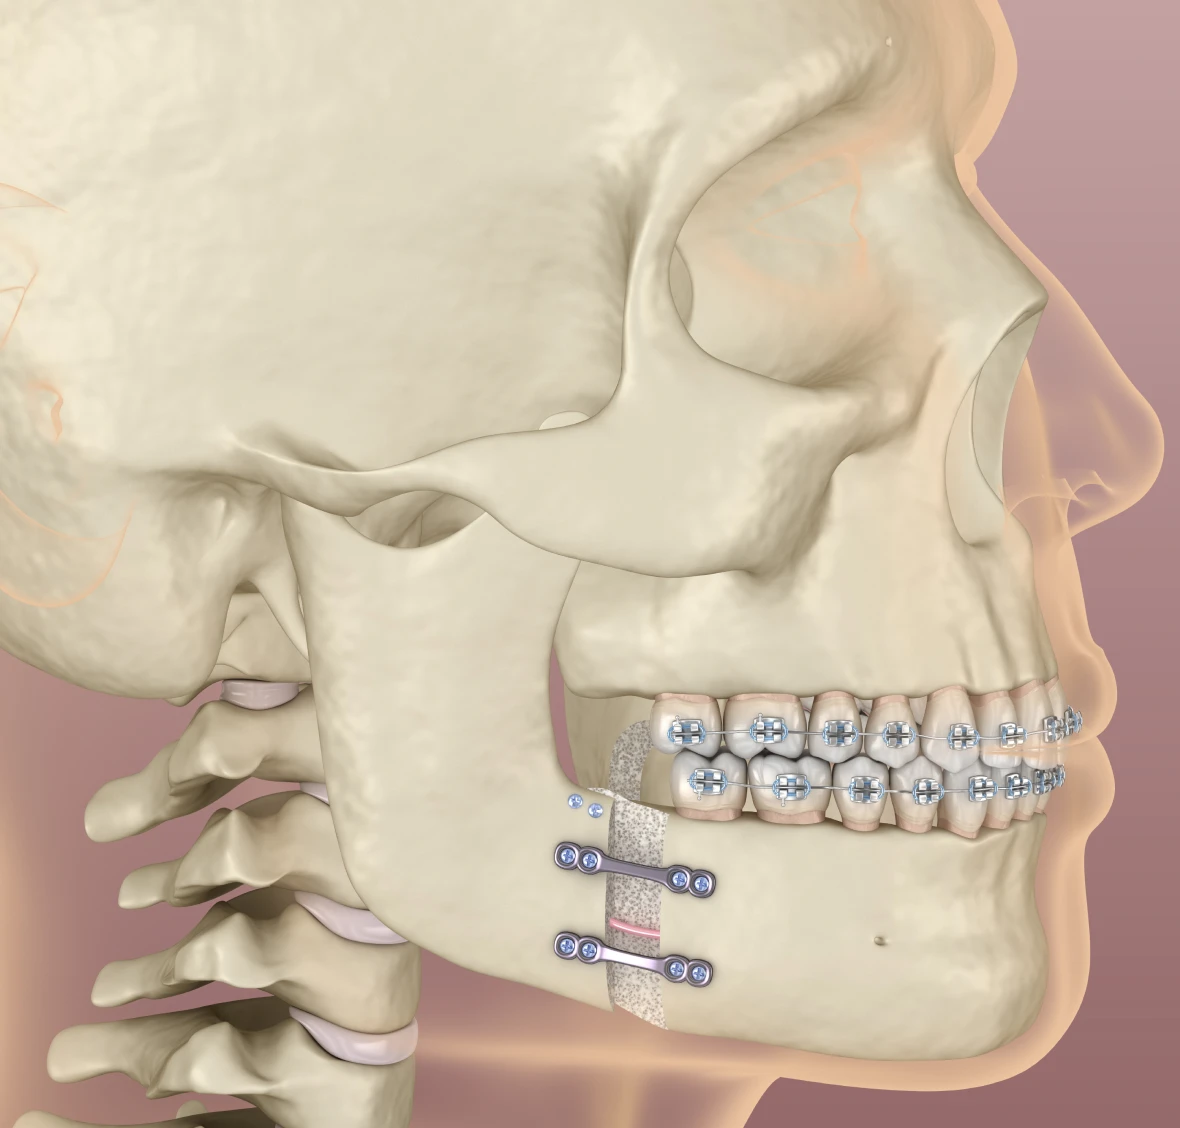

De plus en plus d’adultes choisissent aujourd’hui de bénéficier d’un traitement orthodontique. Les techniques modernes permettent d’allier efficacité, confort et discrétion, afin de répondre aux attentes esthétiques et fonctionnelles des patients. L’orthodontie adulte ne se limite pas à l’alignement des dents : elle contribue également à améliorer l’occlusion, à préserver la santé des gencives et à optimiser la fonction masticatoire.